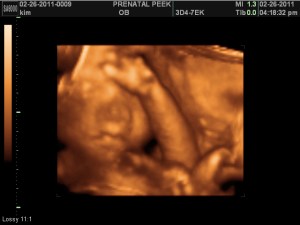

3D Sonogram!!